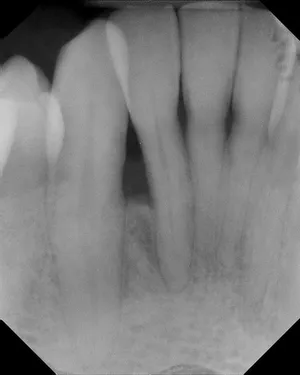

Before and After X-rays